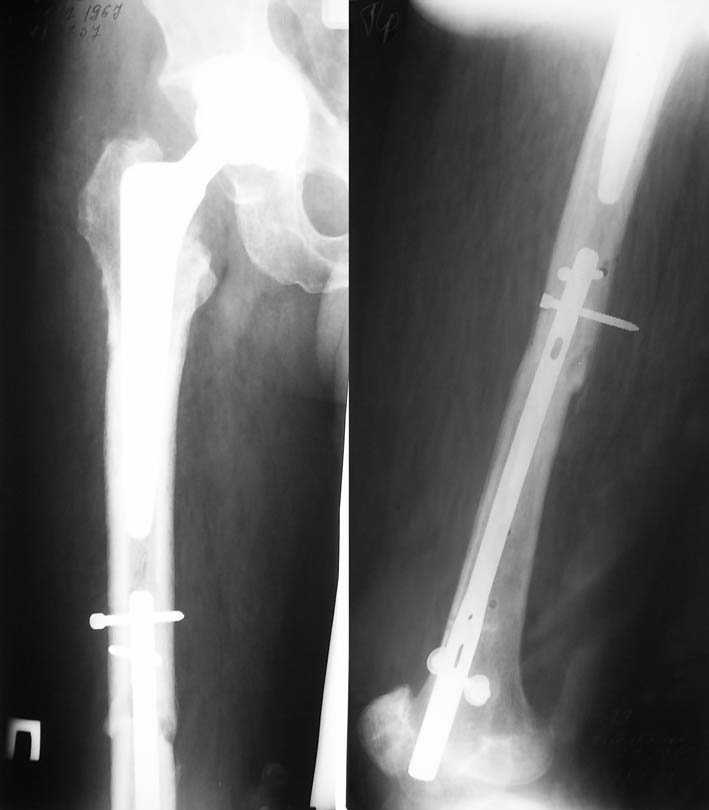

Ошибки случаются, когда игнорируются правила обследования больных с переломом бедра. Часто, когда "экономят" рентген пленки и снимают без надлежащих захватов сустава.

Одним из "золотых" правил при лечении переломов бедра в обязательном порядке до операции необходимо убедиться в отсутствии или наличии перелома шейки.

Отдельный снимок шейки или ЭОП является стандартом обследования. Все сомнительные рентген снимки проверяются тщательно дополнительными срезами КТ.

Из-за опасности вторичного смещения переломов "без смещения" во время интрамедуллярных манипуляций, особенно при ретроградном введении, необходимо каждый случай протоколировать с описанием состояния шейки после операции.

This is very bad situation. To miss fracture subcapital like this is unforgivable. Now the fracture of the femoral shaft isn't healed with malreduction component and fracture of the subcapital femur (doesn't matter what grade) without any chance for healing. More of them, therк is very high chanse to AVN of the femoral head. At the moment nothing can be done exept change of the intramedullary nail in femoral shaft

with femoral neck fixation after open reduction . I mean PF Aesculap nail or TAN Smith & Nerphuy). After that waiting with hoope to union of the femoral shaft fracture and, depending on condition of the femoral head, in the life - suprise, or go to THR noncemented if the head will be dead. Any way this young man is invalid. Good luck !